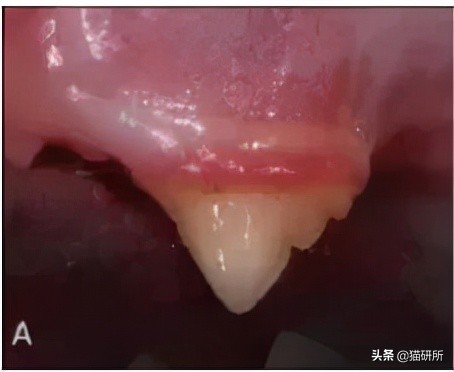

牙龈炎 (A)、牙周炎 (B) 牙周炎会出现牙龈萎缩,齿根暴露 图自:researchgate